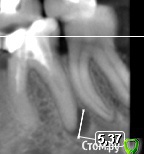

ceti Опубликовано 21 декабря, 2015 Автор Поделиться Опубликовано 21 декабря, 2015 Здравствуйте! По результатам очного осмотра доктор исключил трещину и предположил парадонтальную проблему. Есть какое-то объяснение, что могло послужить причиной и почему процесс так быстро прогрессировал? Ниже фрагмент КТ, который был сделан в феврале этого года и свежий снимок: Заранее благодарю. Ссылка на комментарий